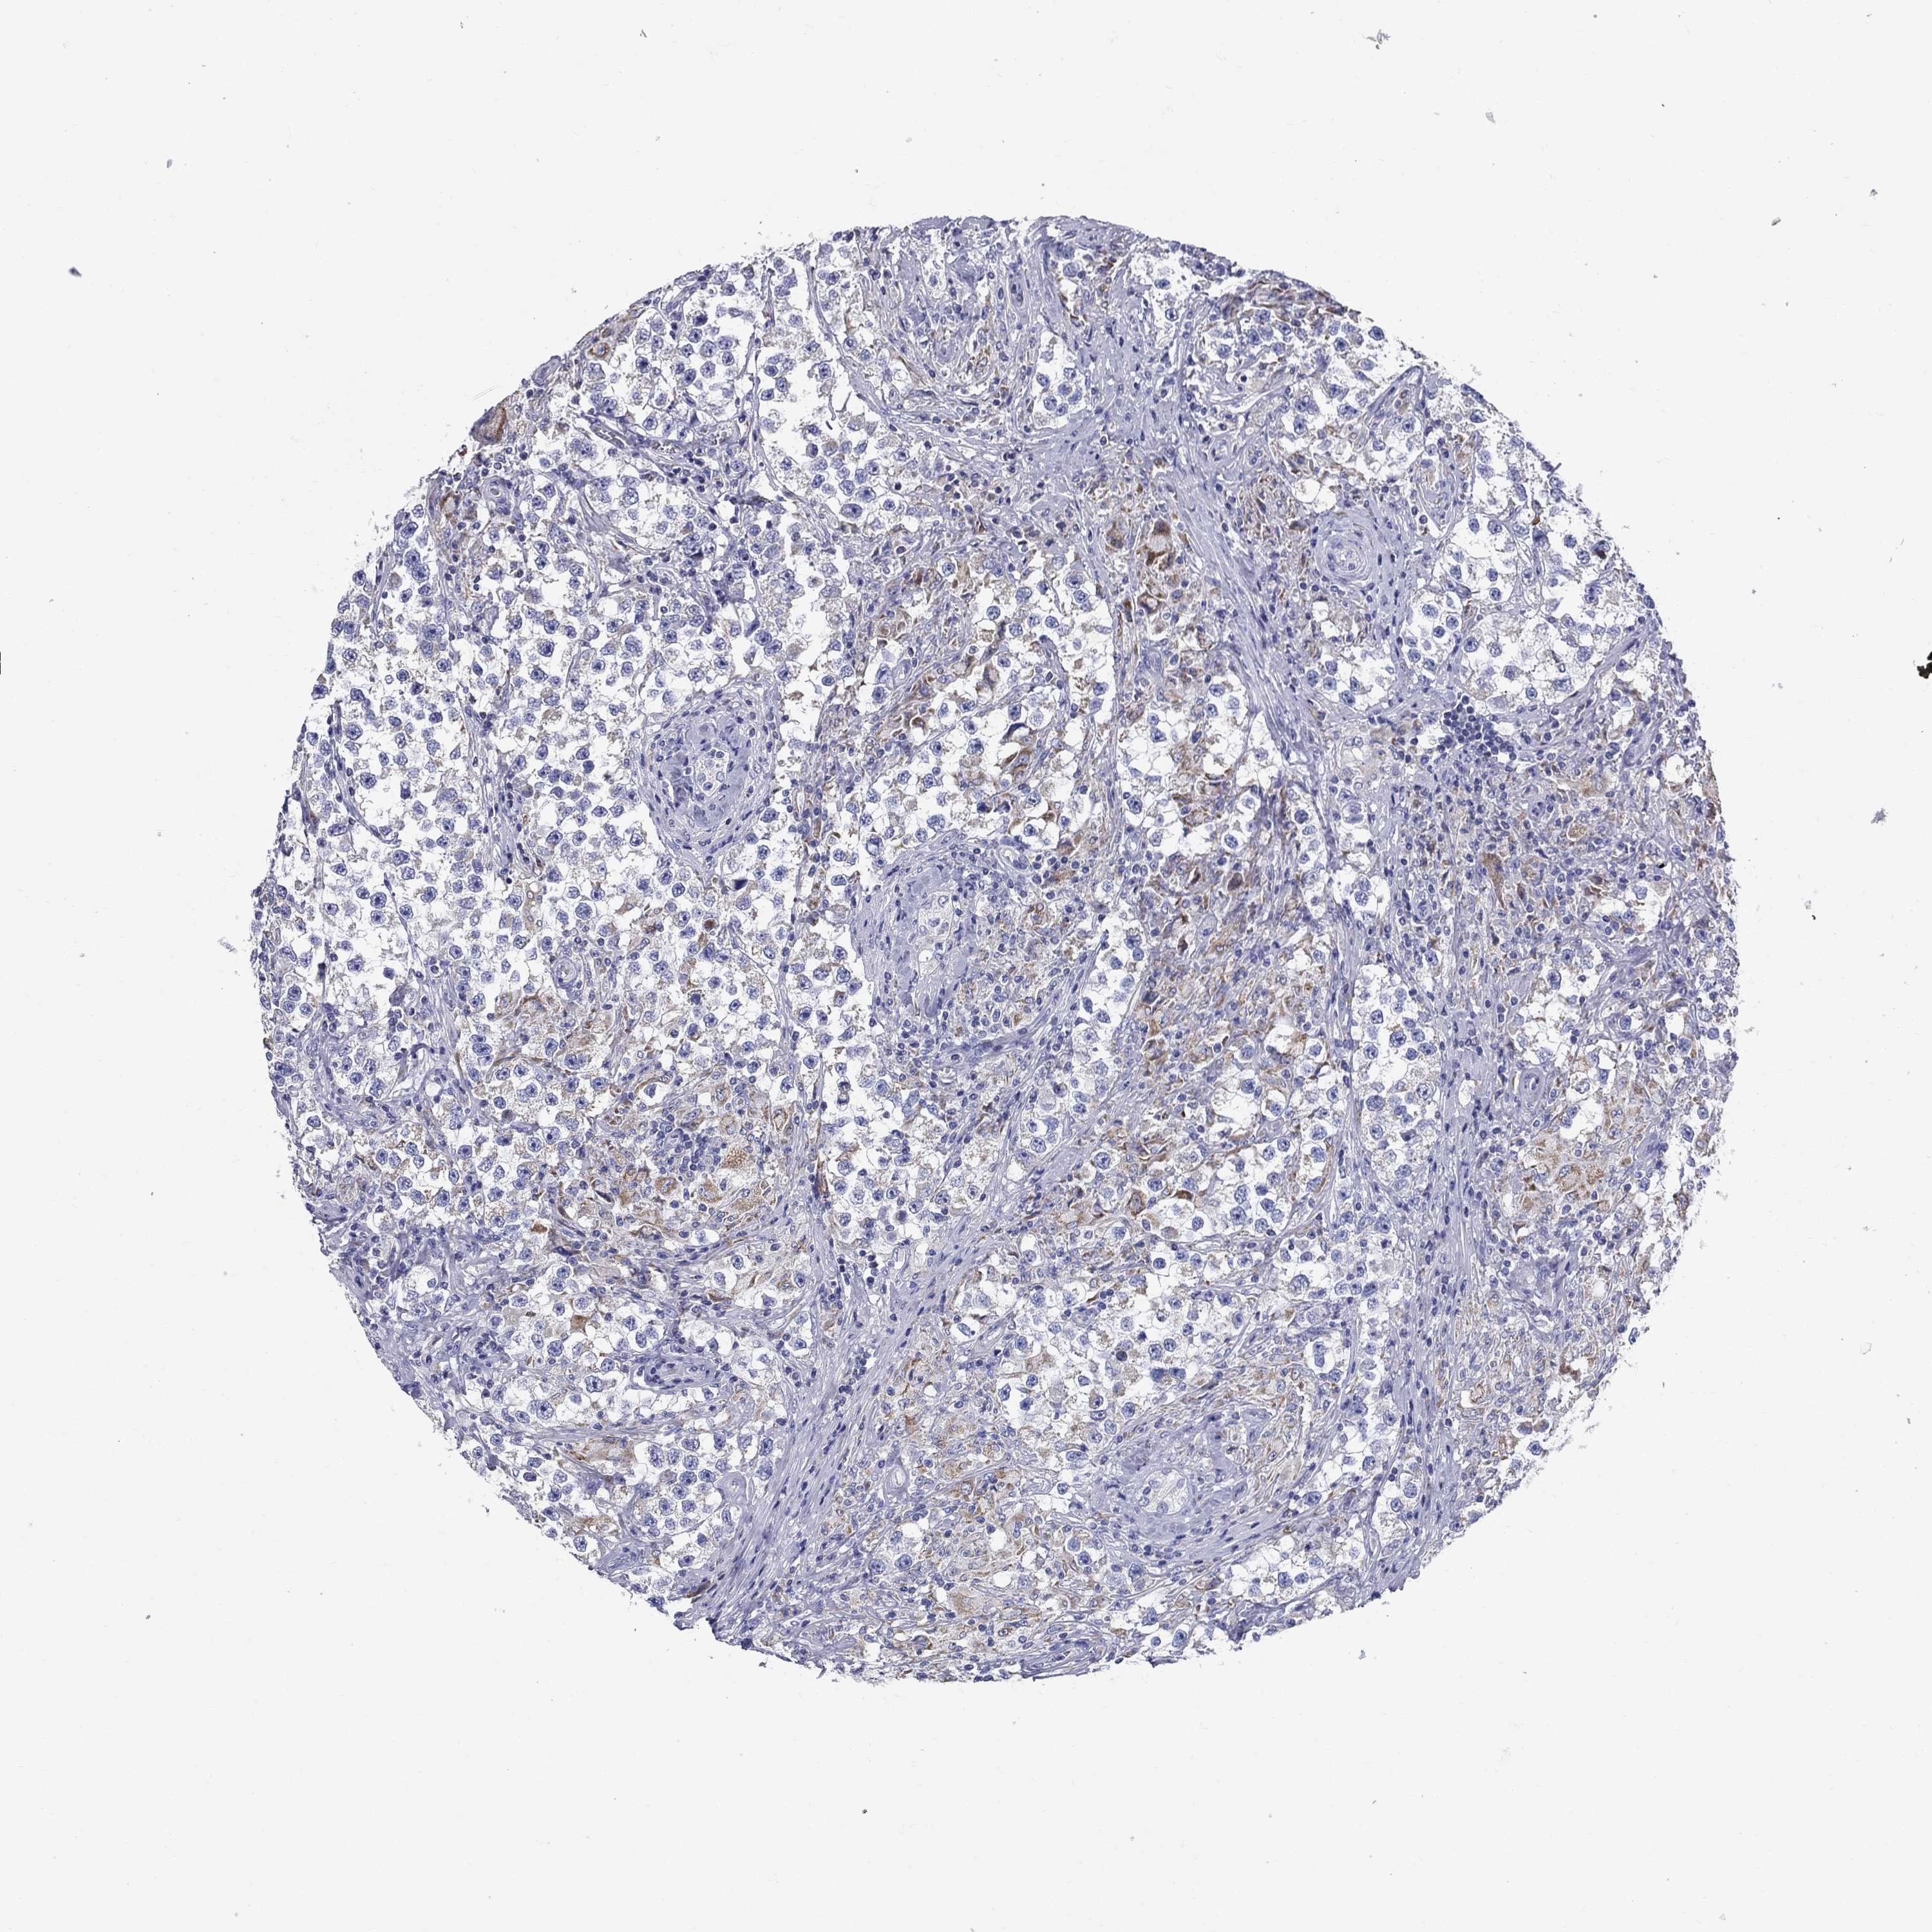

TESTIS CANCER - Protein expressioni

A mouse-over function shows sample information and annotation data. Click on an image to view it in a full screen mode. Samples can be filtered based on level of antibody staining by selecting one or several of the following categories: high, medium, low and not detected. The assay and annotation is described here.

Note that samples used for immunohistochemistry by the Human Protein Atlas do not correspond to samples in the TCGA dataset.

Antibody stainingi

Antibody staining in the annotated cell types in the current human tissue is reported as not detected, low, medium, or high, based on conventional immunohistochemistry profiling in selected tissues. This score is based on the combination of the staining intensity and fraction of stained cells.

Each image is clickable and will lead to virtual microscopy that enables deeper exploration of all samples and also displays staining intensity scores, fraction scores and subcellular localization as well as patient and tissue information for each sample.

Antibody HPA076321

Carcinoma, Embryonal, NOS